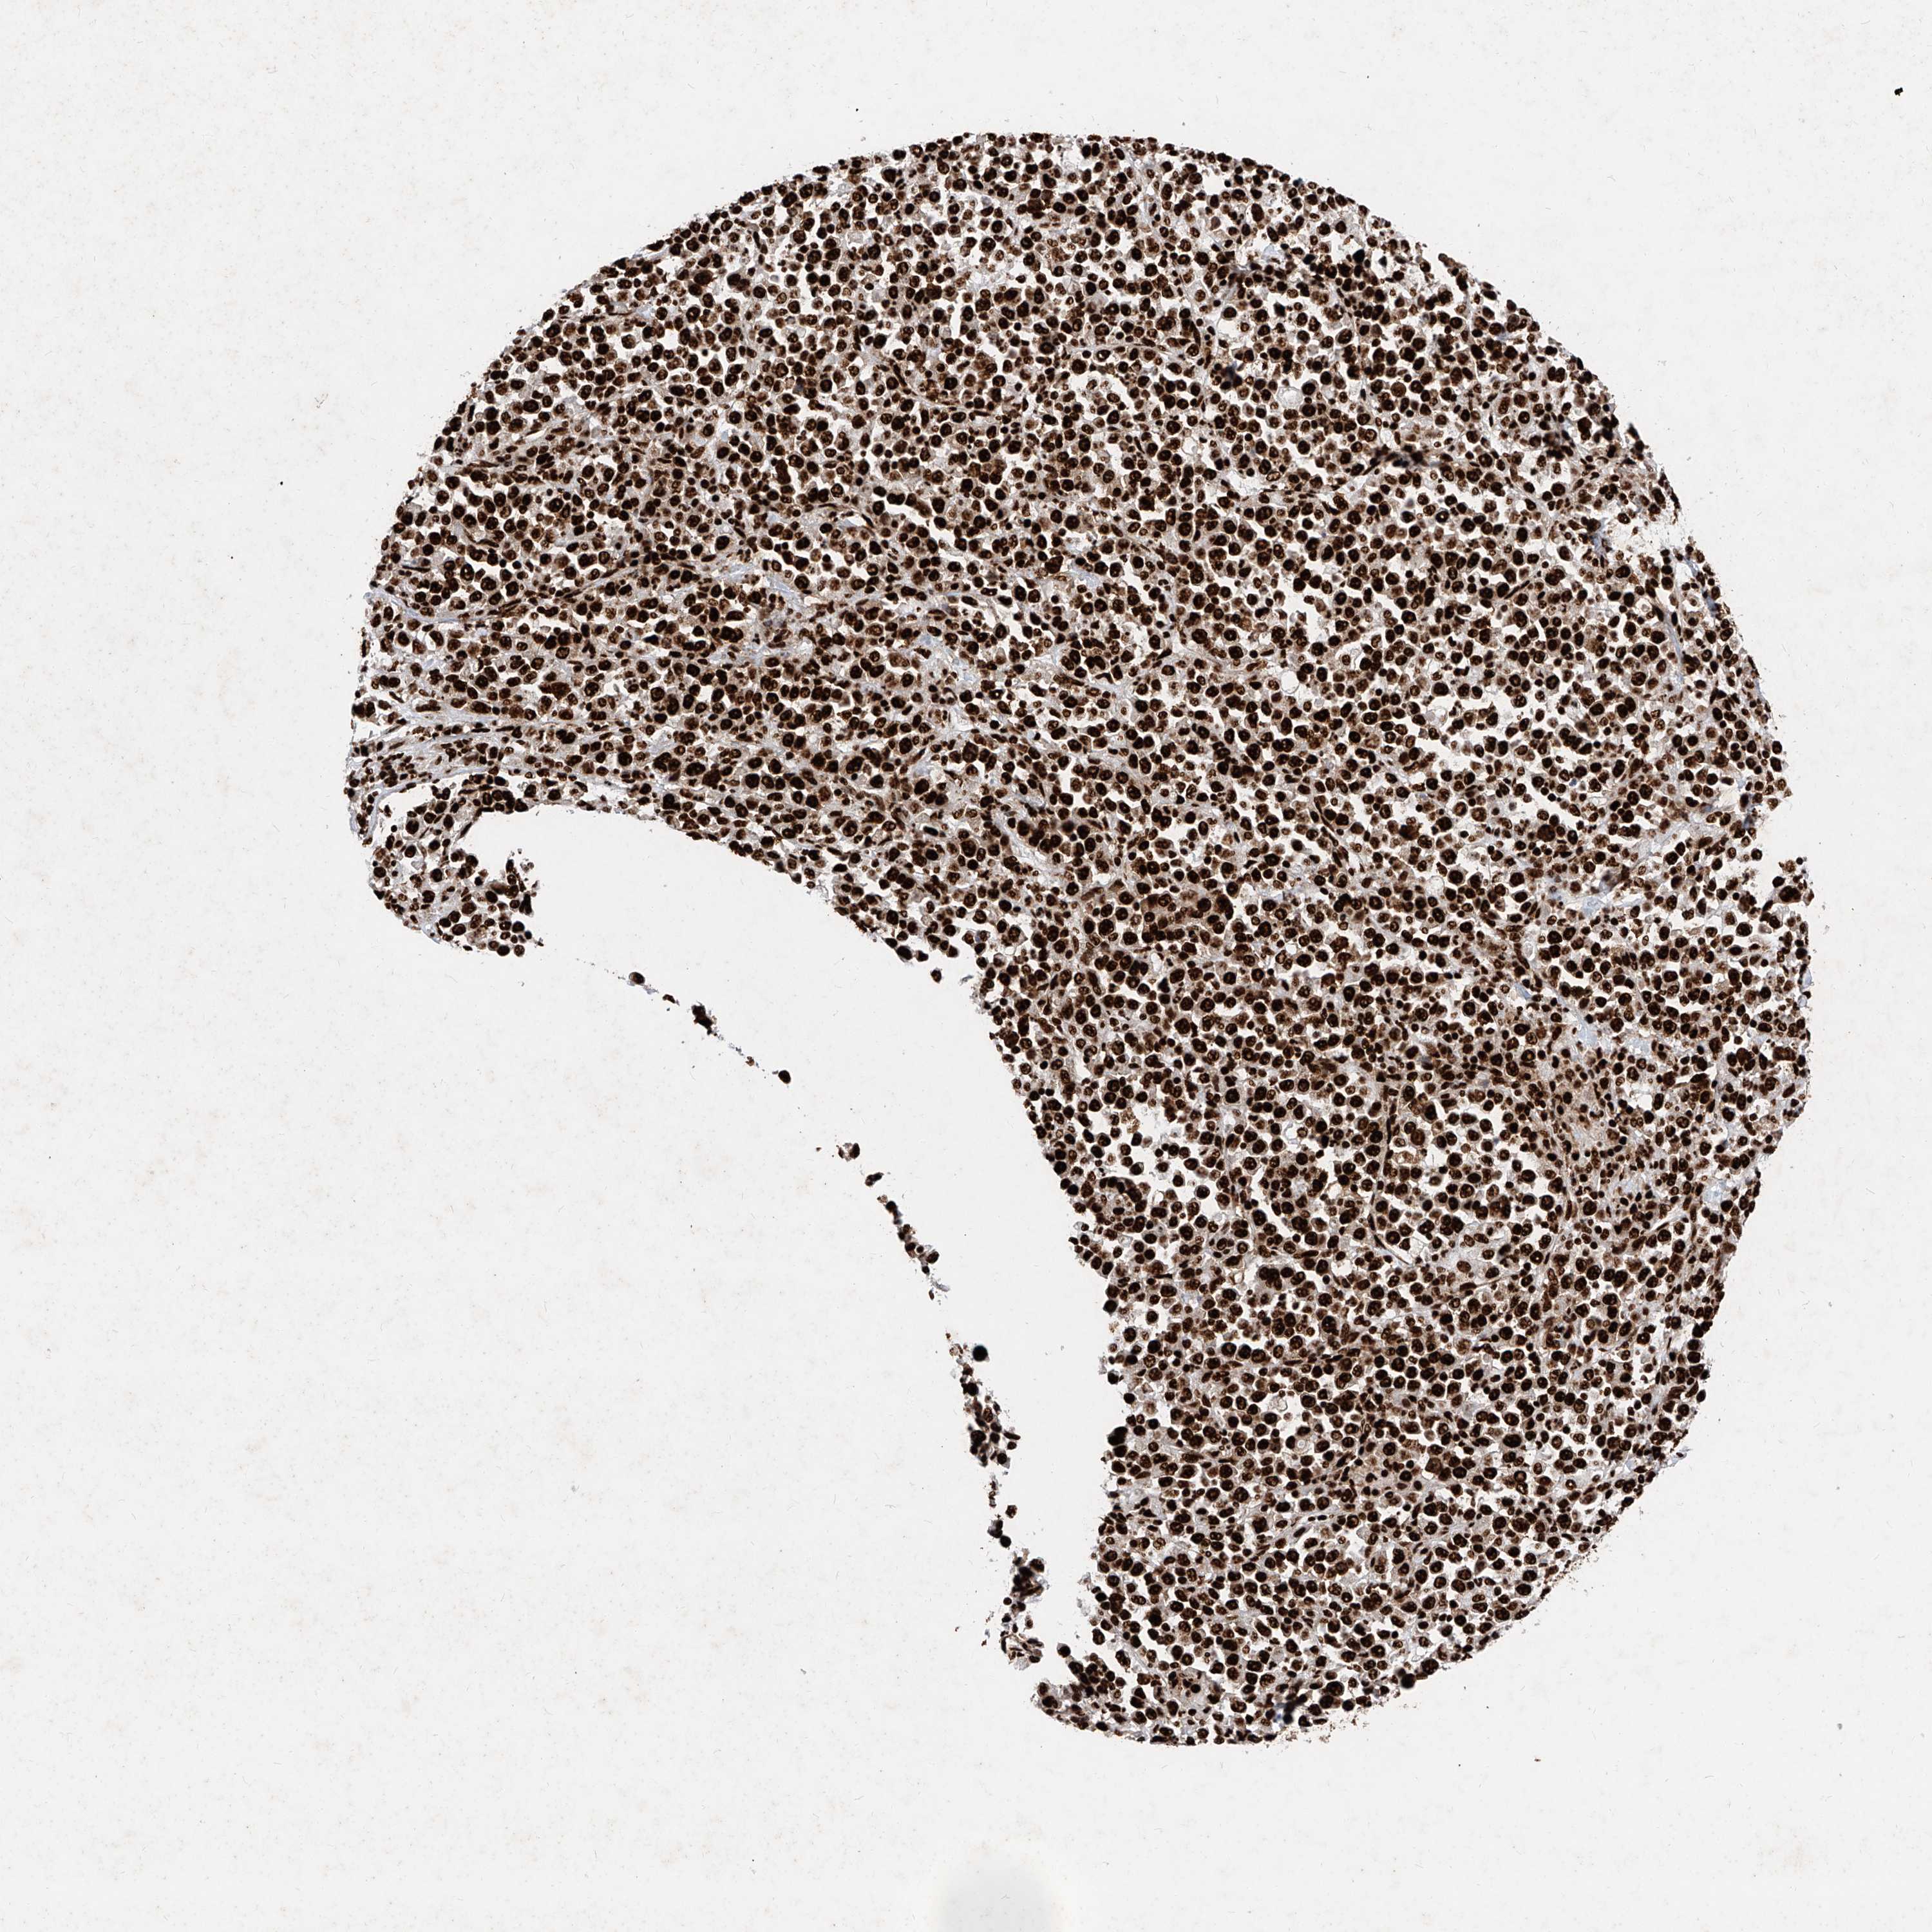

STOMACH CANCER - Protein expressioni

A mouse-over function shows sample information and annotation data. Click on an image to view it in a full screen mode. Samples can be filtered based on level of antibody staining by selecting one or several of the following categories: high, medium, low and not detected. The assay and annotation is described here.

Antibody stainingi

Antibody staining in the annotated cell types in the current human tissue is reported as not detected, low, medium, or high, based on conventional immunohistochemistry profiling in selected tissues. This score is based on the combination of the staining intensity and fraction of stained cells.

Each image is clickable and will lead to virtual microscopy that enables deeper exploration of all samples and also displays staining intensity scores, fraction scores and subcellular localization as well as patient and tissue information for each sample.

Antibody HPA029005

Antibody CAB034889

Staining

High

Medium

Low

Not detected

Intensity

Strong

Moderate

Weak

Negative

Quantity

>75%

75%-25%

<25%

None

Location

Nuclear

Cytoplasmic/membranous

Cytoplasmic/membranous,nuclear

Adenocarcinoma, NOS